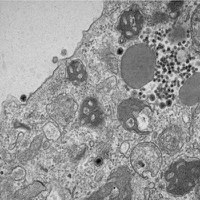

• Bolsista da CAPES descobre yaravirus brasiliensis, que infecta amebas

Bolsista da CAPES descobre yaravirus brasiliensis, que infecta amebas

18/03/2020